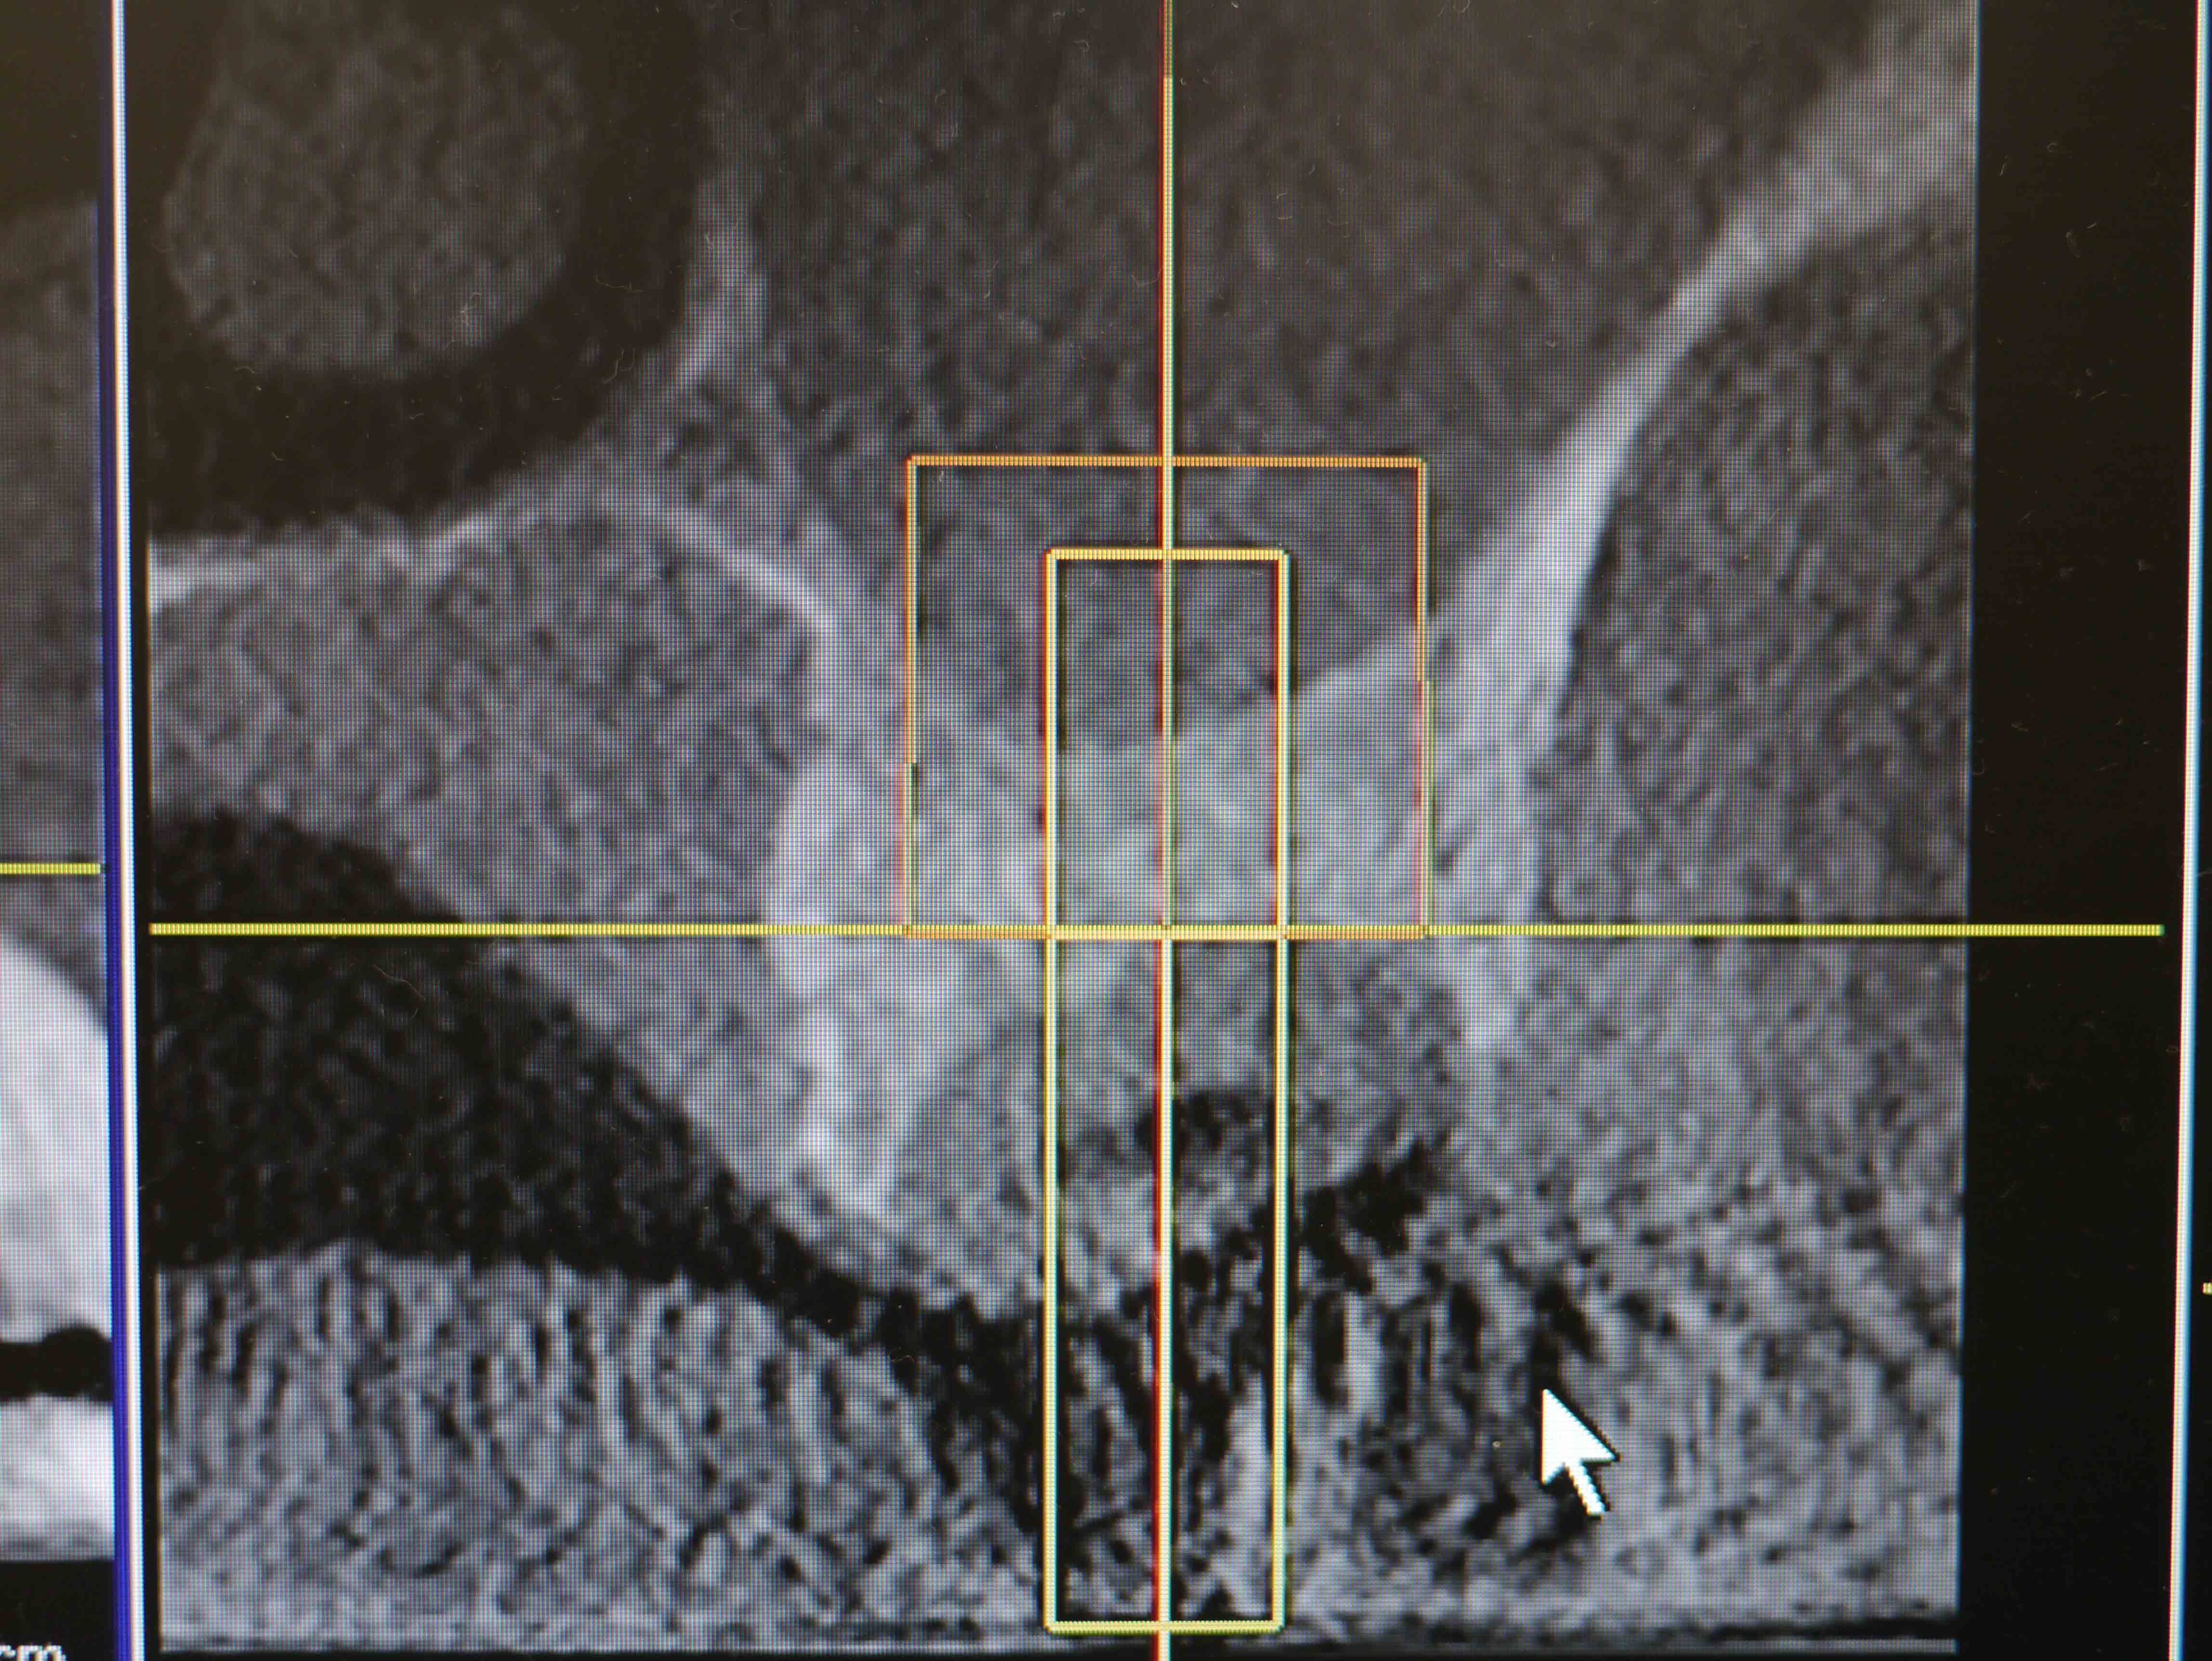

CT画像2

右上7番埋入予定の骨を後側から見たCT画像

CT画像3

右上6番埋入予定の骨を後側から見たCT